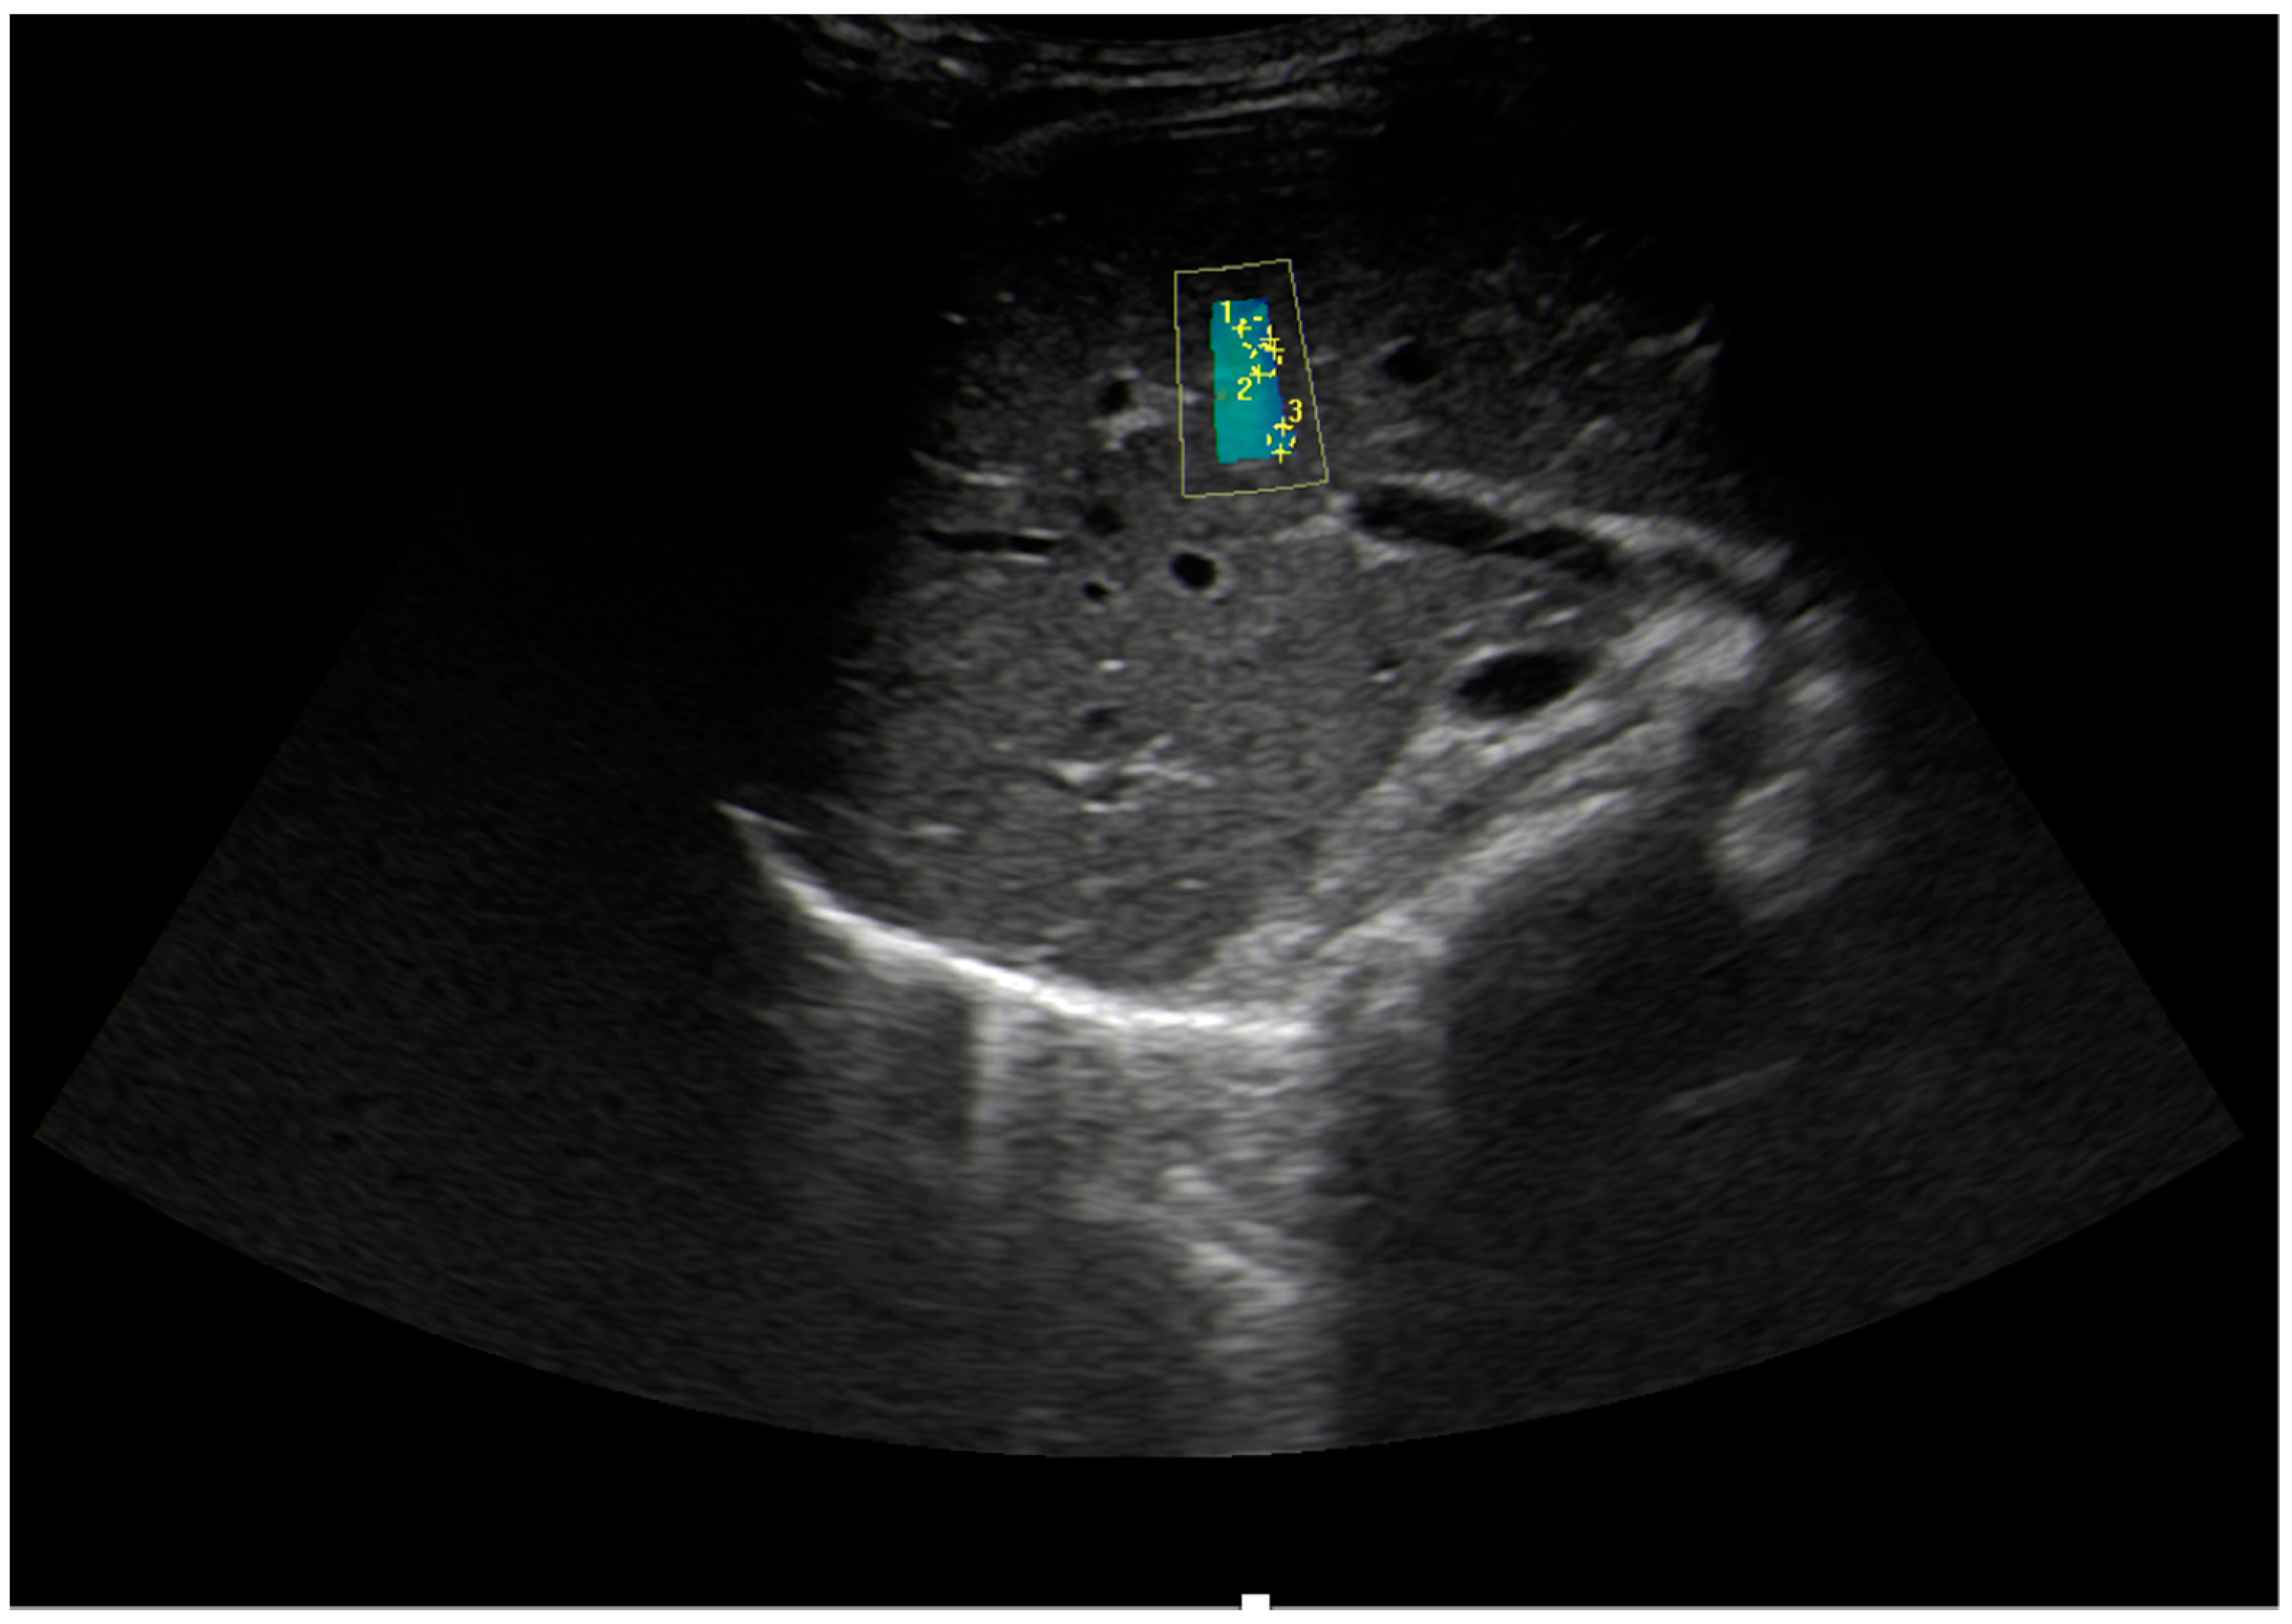

| Mărginean et al., 2019, Romania [19] | Prospective 210/77 | 11.29 ± 3.83 y—normal weigh 10.44 ± 3.38 y—obese | TE 2D-SWE | 3.80 ± 0.48 kPa 3.73 ± 0.48 kPa 1.09 ± 0.09 m/s | 4.23 ± 0.53 kPa 3.84 ± 0.35 kPa 1.18 ± 0.09 m/s | p < 0.0001 p = 0.0314/p < 0.0001 AUC: V median: 0.817 ± 0.028 (p = 0.0001); TE: 0.730± 0.033 (p = 0.0001) |